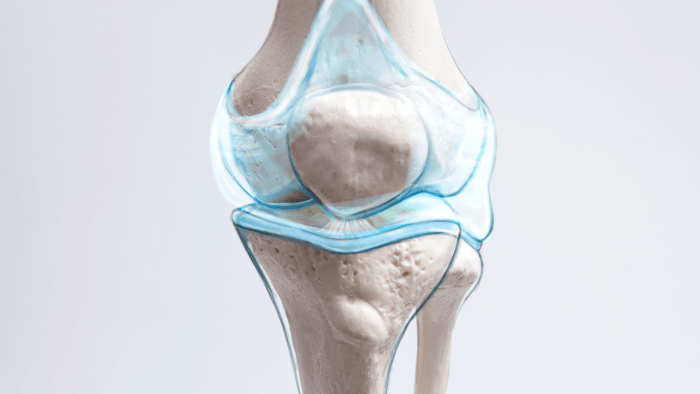

Normal Joint Anatomy and Function

person pointing at knee joint model

To really understand what arthritis does to your body, it helps to first know what a healthy joint looks like and how it functions. A joint is defined as a region where two bones contact each other. (5) Think of them as finely tuned machines that are complex, elegant, and designed for smooth, pain-free movement. When all parts are working in harmony, you hardly notice them. But when something goes wrong, every step, reach, or twist can become a painful reminder that something’s out of sync.

Let’s take a quick tour of the key players inside your joints, so you can better appreciate what arthritis disrupts and why movement starts to hurt.

Articular Cartilage: The Literally Smooth Operator

stylized image of knee joint showing articular cartilage

This is the glossy, white tissue that covers the ends of bones where they meet at the joint. (6) Articular cartilage is made of a specialized type of connective tissue that’s incredibly smooth and resilient. Its job is twofold:

• Cushioning: It absorbs impact every time you walk, run, jump, or even just stand up.

• Friction reduction: It allows bones to glide over one another with minimal resistance.

In a healthy joint, cartilage is like a well-oiled ice rink, it lets everything slide with ease. But this tissue doesn’t have its own blood supply, which means it doesn’t heal well once damaged. (6) That’s part of what makes arthritis, especially osteoarthritis, so stubborn and progressive once it begins.